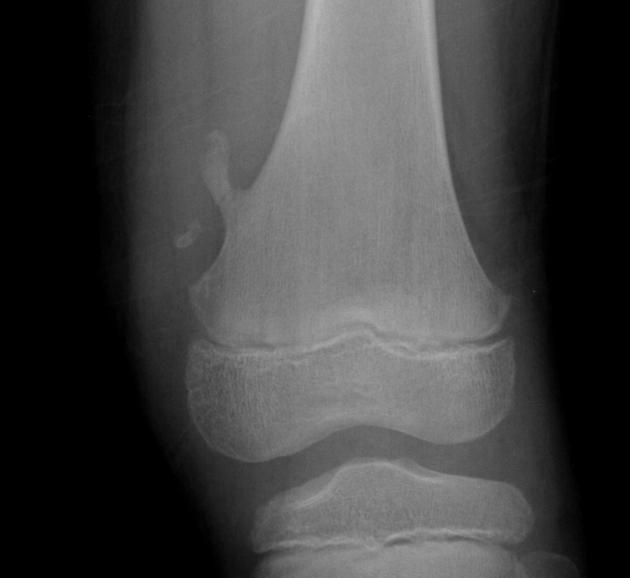

How does the proximal femur look in anatomic position

Femoral necks partially foreshortened

Lesser trochanters partially visible

How does the proximal femur look in internal rotation?

Toes in, heels out

Lesser trochanters not/barely visible, greater trochanters in profile

How does the proximal femur look in external rotation?

Femoral neck greatly foreshortened

Lesser trochanters visible internally

The most common benign bone tumor - arises from the growth zone between the epiphysis and diaphysis of long bones (Metaphysis). Most commonly involves the lower femur or upper tibia and is capped by growing cartilage. Many time it is asymptomatic unless the affected long bone is traumatized which results in a pathologic fx. of the diseased bone.

Osteochondroma (Exostosis)